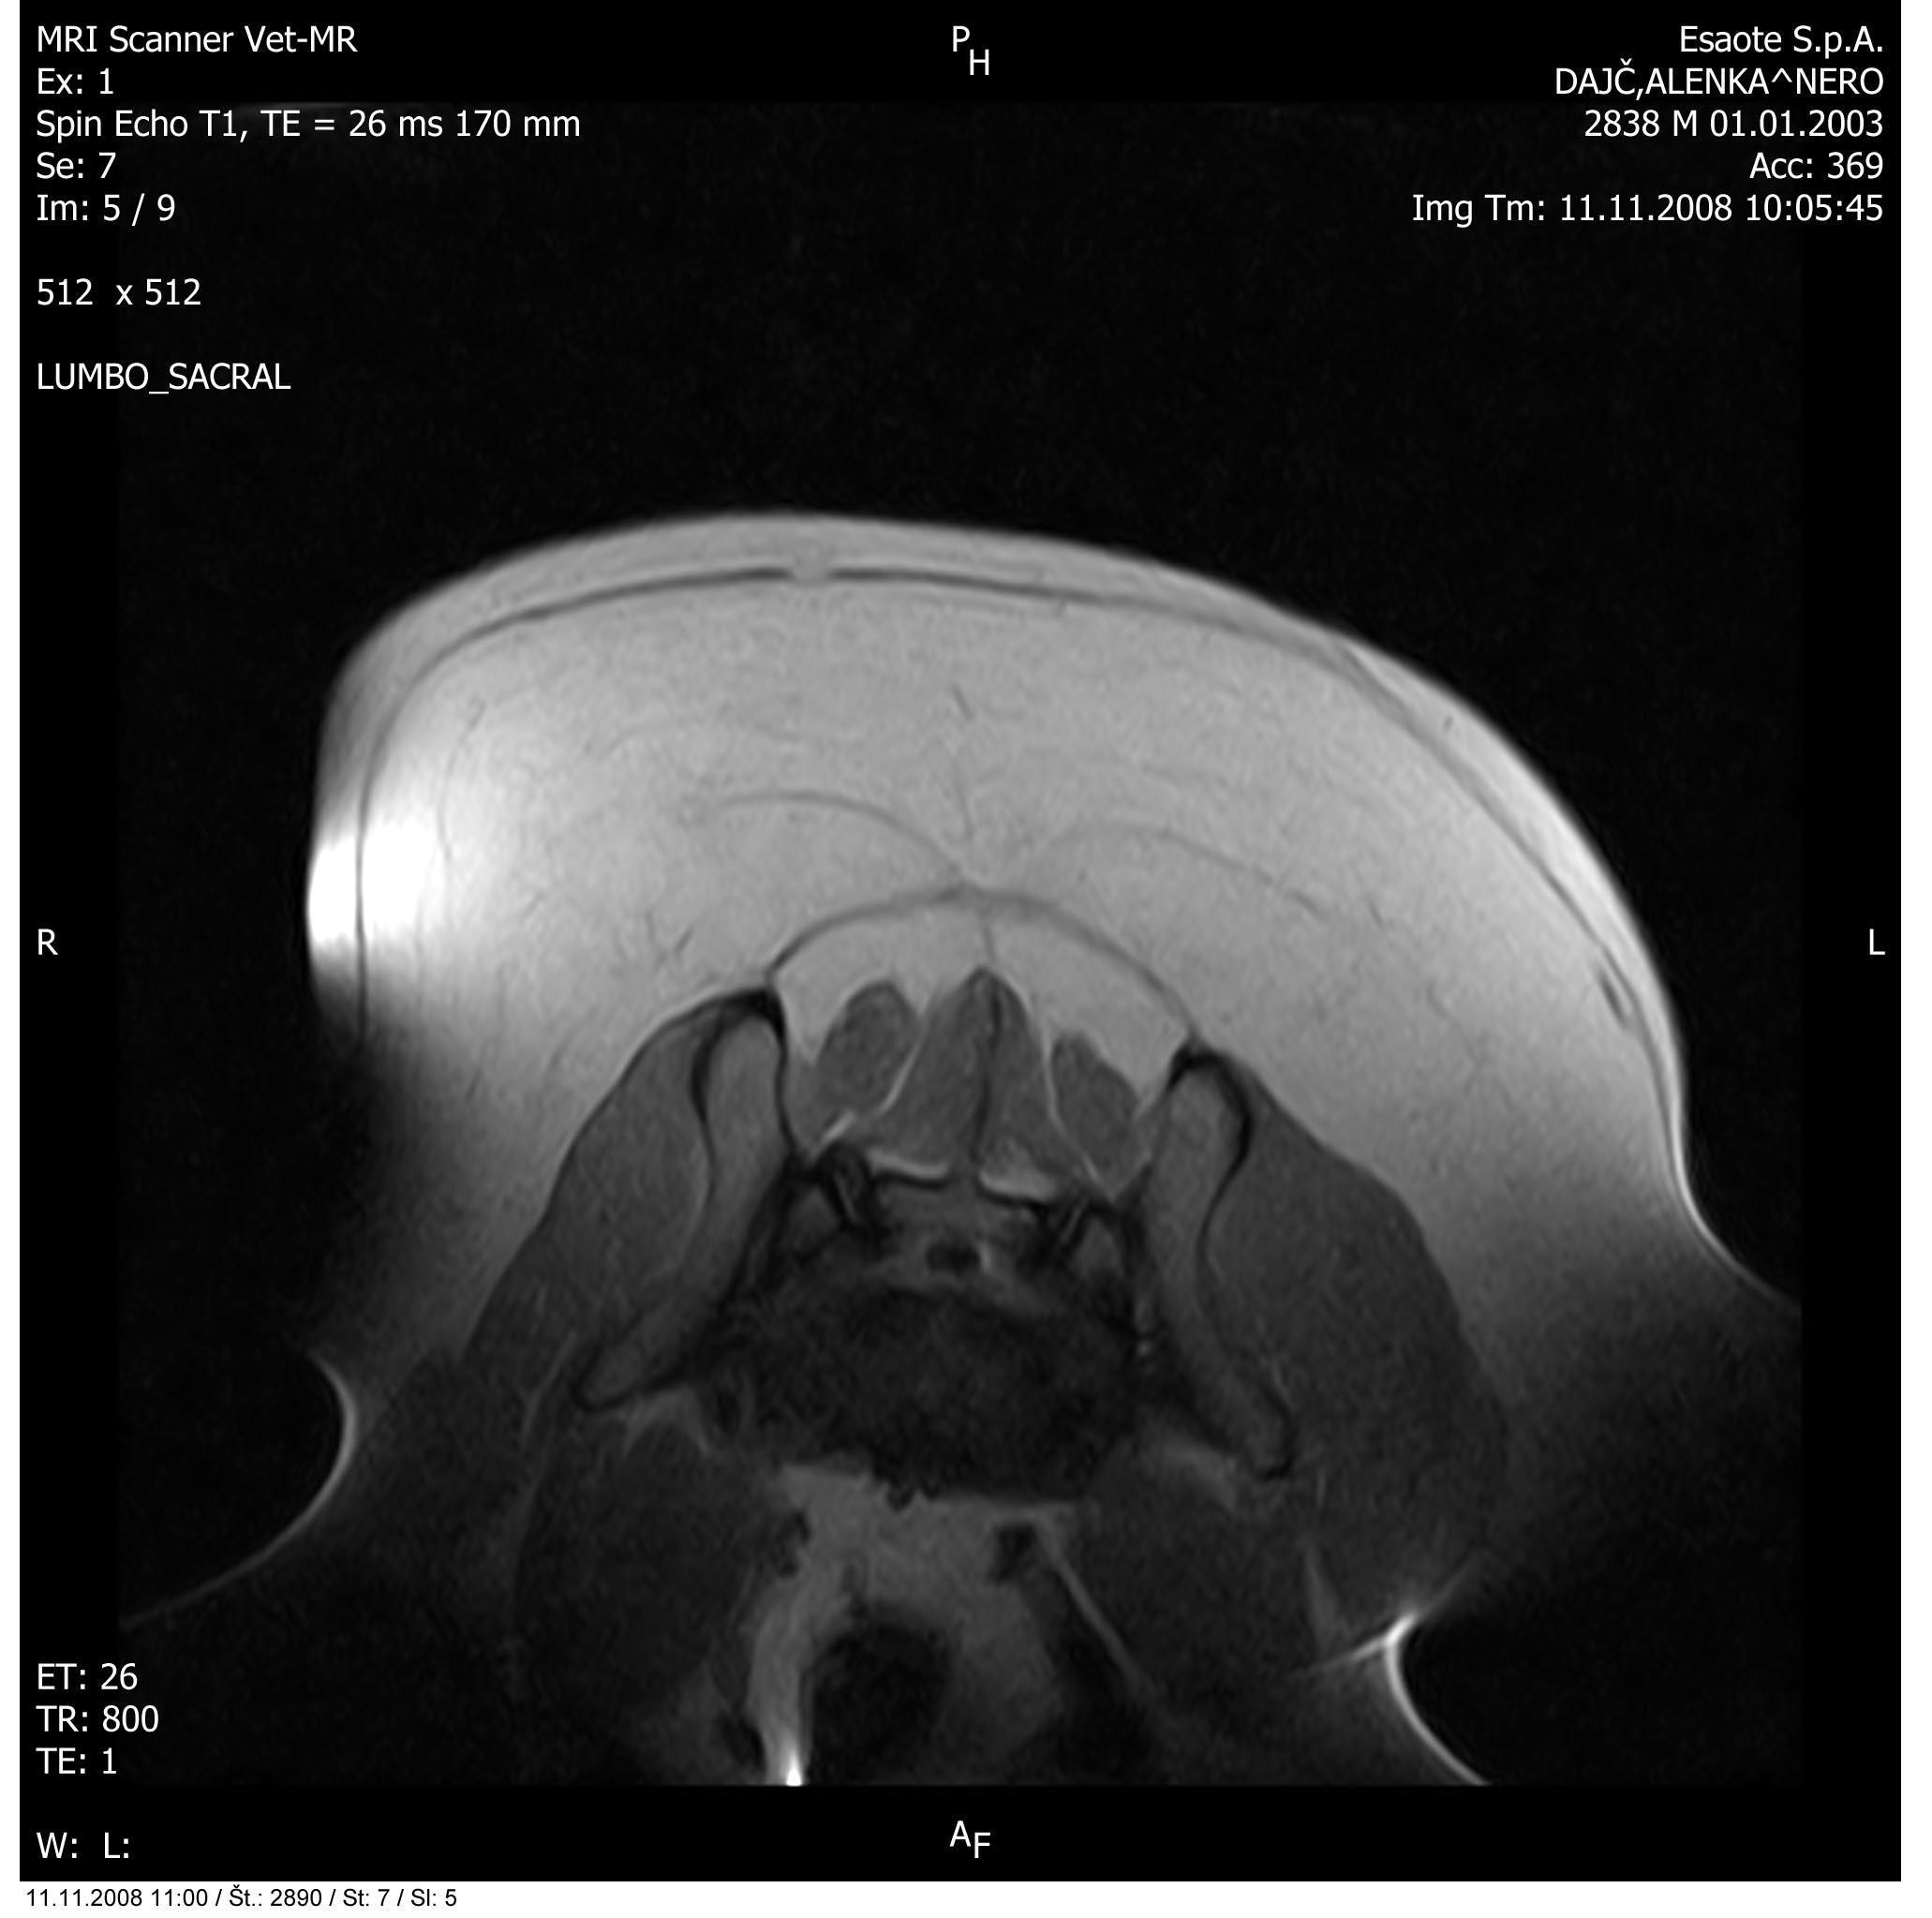

Slika: Primer zdrsa medvretenčnega diska v ledvenokrižnem področju

Magnetna resonanca je torej diagnostična metoda izbora pri ugotavljanju patoloških dogajanj v mehkih tkivih glave in hrbtenice. O leziji pri MR govorimo o vsakem področju, kjer je signal drugačen kot običajno. Na podlagi ocene slik v vseh treh ravninah natančno določimo lokacijo, obseg in vpliv spremenjenih tkiv na okolna tkiva.

Zanima nas število lezij, njihova oblika, robovi, vraščenost, ugotavljamo prirojene ali pridobljene anomalije (na primer hidrocefalus, siringomielija in drugo), potrdimo tipe lezij: degenerativne (na primer starostna atrofija, degenerativna mielopatija, bolezni medvretenčnih diskov in drugo), tumorozne (na primer meningiomi, gliomi, metastaze in drugo), vnetne (na primer meningoencefalitis, diskospondilitis in drugo), žilne (infarkti, poškodbe, embolija diska in drugo) ter druge.